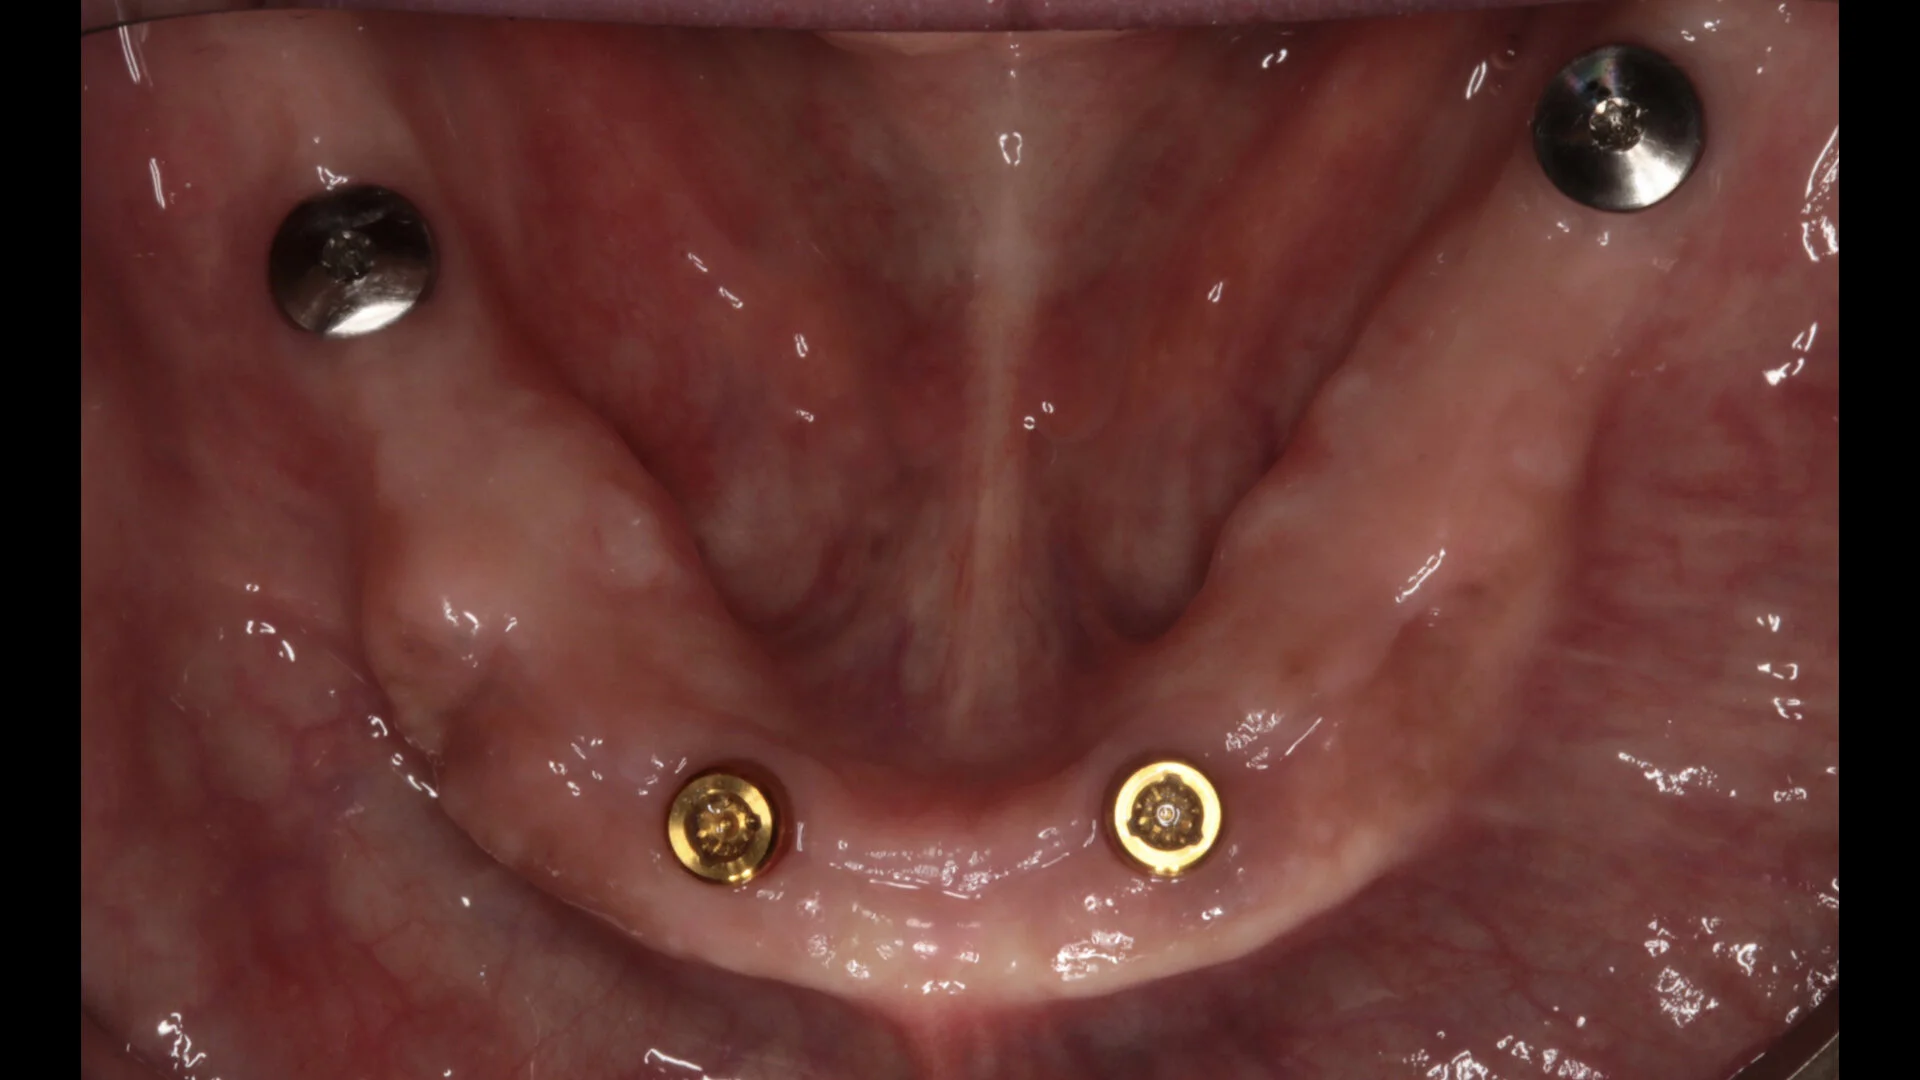

• Mucosal- and implant-borne removable prostheses

• Attachment choice and design

• Bar design